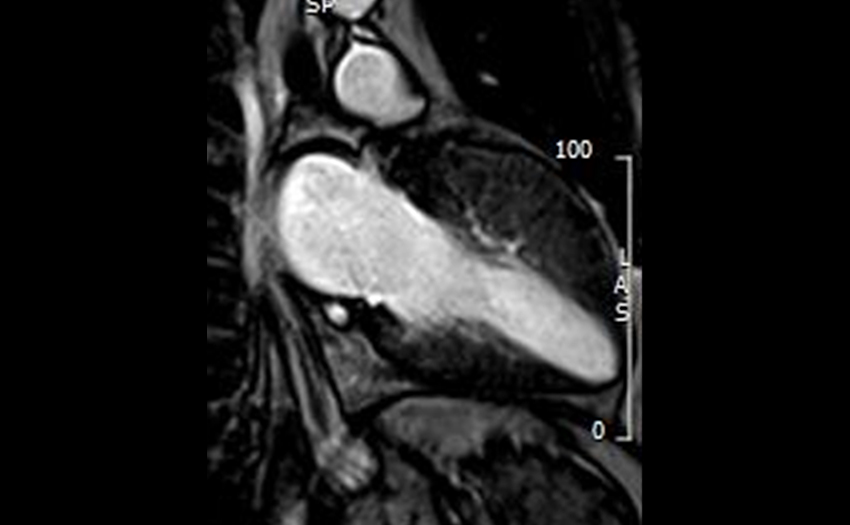

- Advanced Echocardiography: State of the art training on 3D TTE/TEE, Strain, Structural/Interventional Echocardiography. Participation in the latest clinical trials and latest structural interventions. Unparalleled interventional echo experience: (600 TAVR per year, 100 mitral interventions per year, 300 left atrial appendage occlusions per year, 50 tricuspid interventions per year).

- Cardiac MRI: Additional training possible in Cardiac MRI in collaboration with both the Cardiology and Radiology departments.